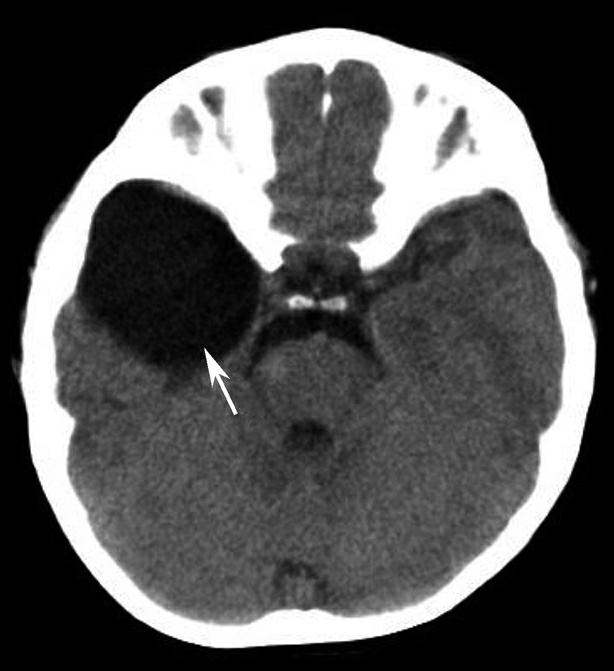

蝶鞍两侧为海绵窦,其内包含颈内动脉及第Ⅲ~Ⅵ对脑神经。海绵窦的密度升高或体积增大常提示病变存在。海绵窦外侧为颞叶,两者之间隔以海绵窦外侧壁。鞍背后方为桥前池及其后方的脑桥,桥前池内可见基底动脉断面,呈圆形稍高密度影。层面中部两侧为颞骨乳突部,其内气化的骨性腔隙为乳突气房。脑桥后方为第四脑室,呈半圆形或新月形,小脑半球的病变(如肿瘤、炎症、出血等)常压迫第四脑室,导致其变形甚至闭塞(图1-2-13)。两侧小脑半球间为小脑蚓部。小脑半球与颞骨乳突部间可见乙状窦。小脑蚓部后方为直窦与上矢状窦汇入窦汇处,窦汇两侧为横窦。静脉窦血栓时可见上述静脉窦增宽、密度明显升高(图1-2-14)。

图1-2-13 第四脑室变形(小脑转移瘤)

A.第四脑室受压变形右移(白箭),提示左侧小脑半球病变;B.左侧小脑半球环形强化结节(黑箭),为瘤体,其周围伴有低密度水肿区